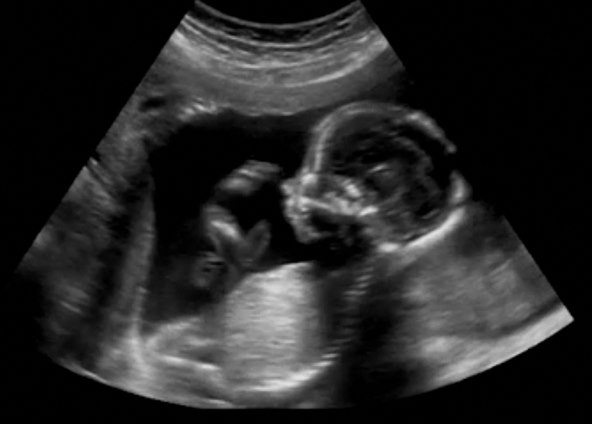

Do 17. tjedana, mozak fetusa počeo je regulirati otkucaje srca u pripremi za život u vanjskom svijetu. Do ovog je trenutka otkucaji srca bili su spontani. Tijekom ultrazvuka u drugom tromjesečju liječnik će provjeriti strukturu bebina srca i provjeriti postoji li kakva urođena greška.

Ako liječniku treba detaljniji pregled bebina srca, preporučit će vam ehokardiografiju između 18. i 24. tjedna trudnoće.